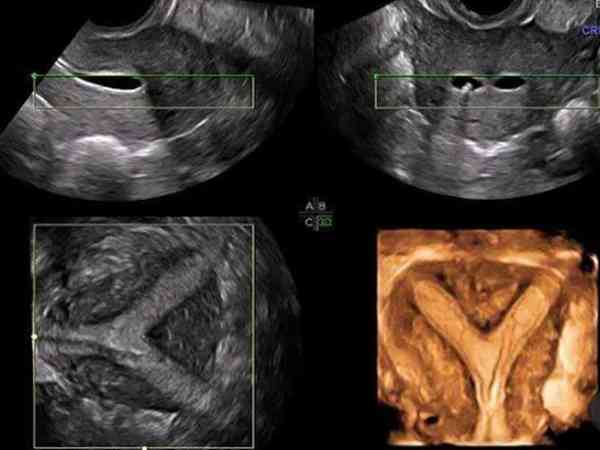

单角子宫超声诊断标准分享,出现这些表现就得注意了

在临床上,单角子宫超声诊断标准为仅一侧附中肾管发育,且多偏向该侧,另一侧附中肾管未发育,这一侧卵巢、输卵管、肾亦往往同时缺如。有时候部分单角子宫女性患者还可能伴随残角,超声表现为一侧腹中肾管发育正常,另一侧发育不完全而成残角子宫,可伴该侧泌尿道发育畸形,下面本...